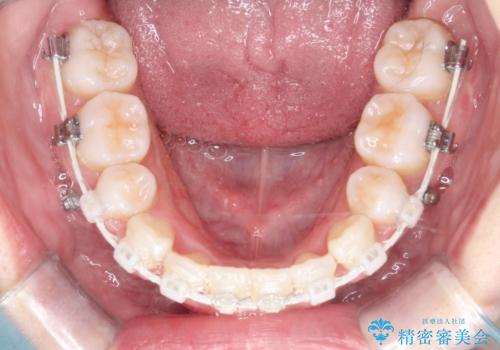

- 矯正装置

- ハーフリンガル

ハーフリンガルワイヤー矯正で治療を開始しました。

ハーフリンガル矯正は、見た目を気にせずに矯正治療ができる方法です。この治療法は、八重歯や前歯のガタツキを効果的に改善します。特徴として、ワイヤーが上の歯の裏側に装着されるため、装置が外から見えません。これにより、治療中も自然な笑顔を保ちながら安心して治療を続けることができます。歯並びの悩みを持つ方にとって、非常に魅力的な選択肢です。